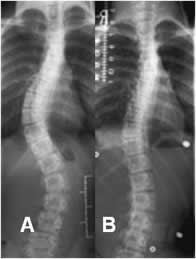

Fig 40. Corsé.

A: Rx AP y B: Rx AP con utilización del corsé. Se aprecia escoliosis dorsolumbar derecha y otra menor dorsolumbar izquierda compensatoria. Ambas cuervas disminuyen de amplitud, cuando se coloca el corsé.